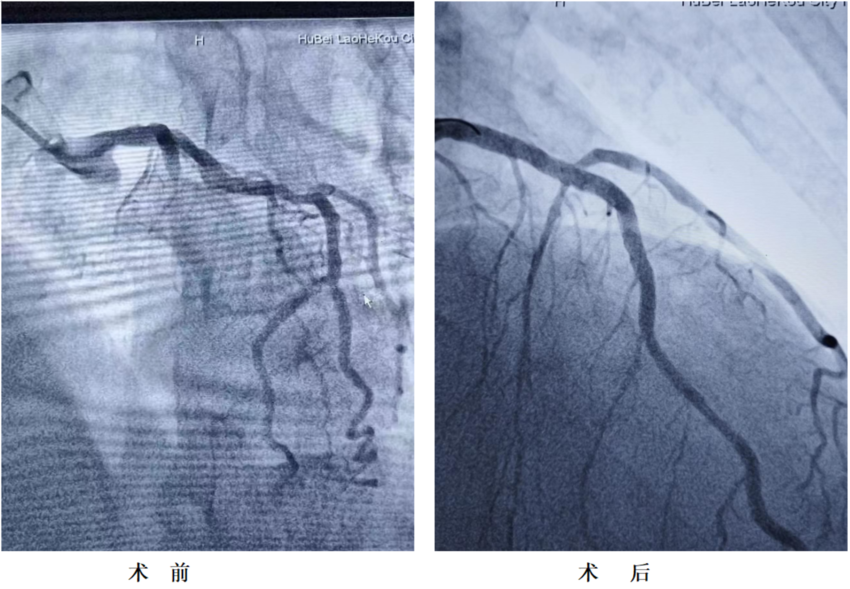

术中造影发现,该患者心脏前降支这条心脏主要供血血管近段闭塞,病情凶险!介入团队凭借精湛的医术,用时20分钟就将导丝通过堵塞的血管并植入支架。心脏血流恢复后,患者症状立刻缓解,转危为安。